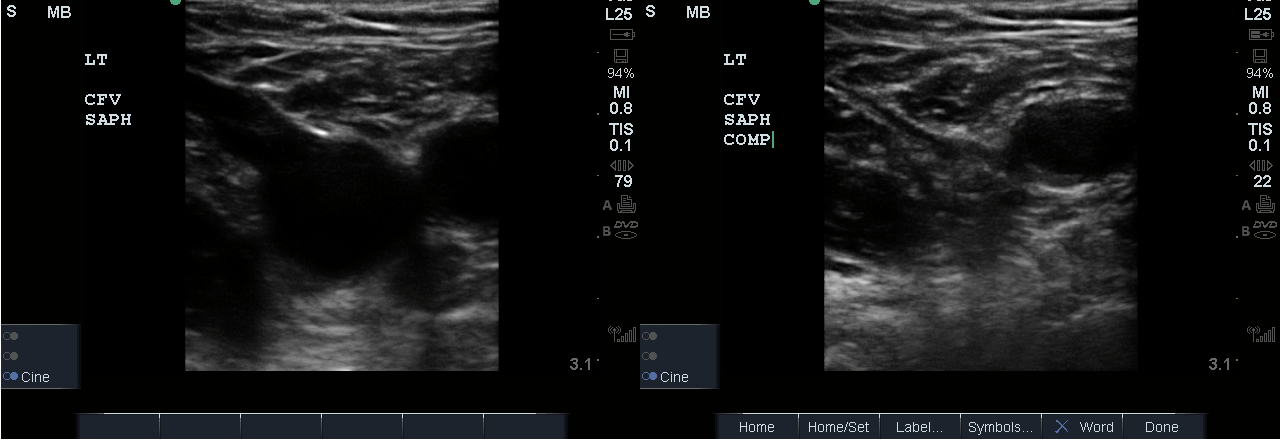

- Identify the inguinal crease at the very proximal medial thigh and place the transducer in a transverse orientation as indicated in Fig. 8. You should see the CFA and CFV as in the corresponding ultrasound image. If you see three vessels (CFA, CFV, SV), you are not proximal enough. Compress the CFV (Fig. 8 and 9).

- Figure 8. Common femoral vein and artery at the inguinal crease with transducer orientation indicated (red rectangle)

- Figure 9. Compression of the common femoral vein at the level of inguinal crease.